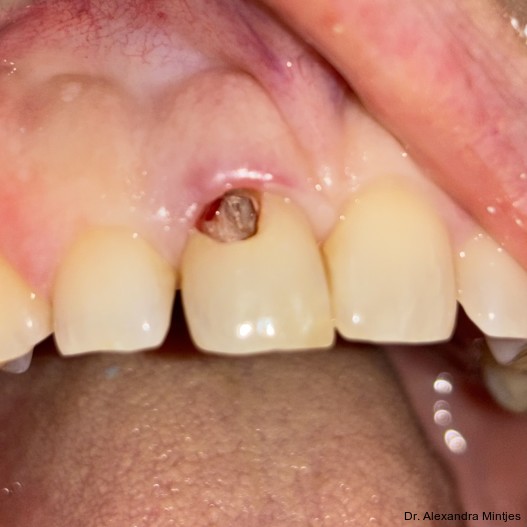

Parodontaler Befund und temporäre Versiegelung

Die Sondierung ergab eine vertikale Defektausdehnung von etwa sechs Millimetern bei einer Taschensondierungstiefe von lediglich zwei Millimetern. Dies wies somit auf eine parodontale Gesundheit hin. Der gereinigte Defekt wurde anschließend mit einem lichthärtenden Flow-Komposit versiegelt, um Unebenheiten auszugleichen und die Adaptation der geplanten CEREC-­Keramikrestauration zu optimieren (Abb. 4).